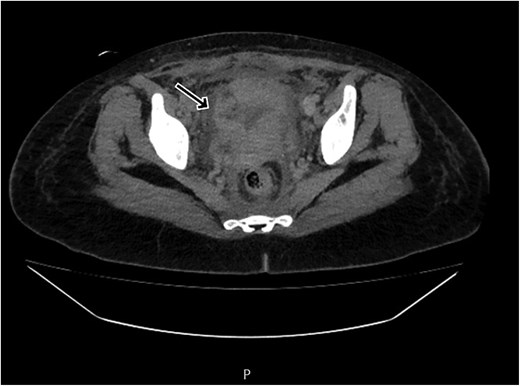

By postpartum day five, the patient exhibited persistent fever and worsening clinical status, unresponsive to broad-spectrum antibiotics. A contrast-enhanced computed tomography (CT) scan was performed, revealing a ruptured uterine scar with omental herniation and a large intra-abdominal abscess (Figs 1 and 2).

CT scan revealing a ruptured uterine scar with omental herniation.